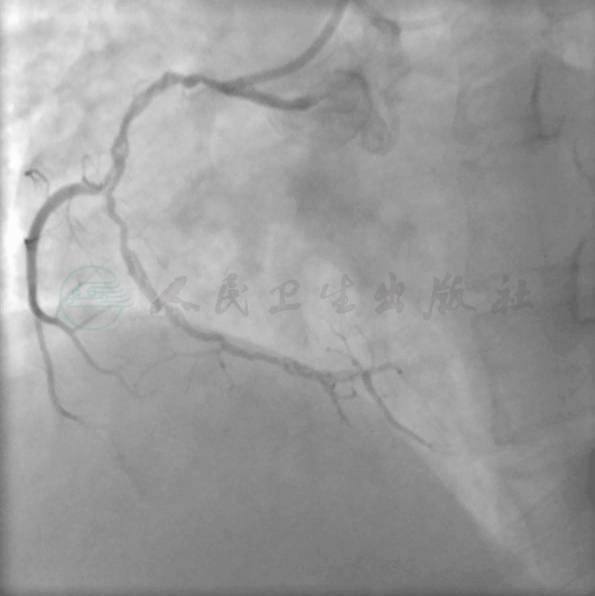

冠状动脉造影结果见图1、图2。病变特点:① RCA从Ⅰ-Ⅱ段拐弯处出现长夹层(图1),双侧同时造影显示闭塞段长度<2cm,但闭塞段近端有分支血管,闭塞段远端为分叉血管(图2);②闭塞时间不长,从病史上推测1个月左右;③左冠脉正常。

图1 RCA从I-II段拐弯处出现长夹层